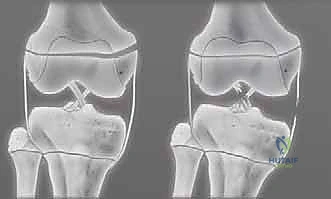

تصنيف كسور صفيحة النمو: نظام سالتر-هاريس (Salter-Harris)

لغة التخاطب بين أطباء جراحة العظام حول العالم تعتمد على نظام تصنيف "سالتر-هاريس". هذا التصنيف لا يصف شكل الكسر فحسب، بل يرشد الأستاذ الدكتور محمد هطيف في تحديد استراتيجية العلاج الدقيقة وتوقع النتائج المستقبلية لنمو الطفل.

ينقسم هذا التصنيف إلى خمسة أنواع رئيسية، وسنشرحها هنا بالتفصيل المطبق على عظم الفخذ البعيد:

النوع الأول (Type I) والنوع الثاني (Type II): الكسور خارج المفصل

هذه كسور انفصالية تحدث خارج نطاق السطح المفصلي للركبة.

* النوع الأول (I): يمر الكسر أفقياً بالكامل عبر طبقة الخلايا المتضخمة في صفيحة النمو، مما يفصل المشاشة عن الكردوس دون كسر العظم نفسه. قد لا يظهر في الأشعة السينية بوضوح إذا لم يحدث انزياح.

* النوع الثاني (II): هو الأكثر شيوعاً. يمر الكسر عبر صفيحة النمو ثم ينحرف صعوداً ليكسر جزءاً مثلثاً من عظم الكردوس. هذه القطعة العظمية المثلثة تُعرف طبياً باسم "شظية ثورستون-هولاند" (Thurston-Holland fragment).

* التوقعات: على الرغم من أن هذه الأنواع عادة ما يكون لها تشخيص أفضل للنمو مقارنة بالأنواع الأخرى، إلا أن كسور الفخذ البعيدة تحديداً تكون أكثر عرضة لاضطرابات النمو (بنسبة تصل إلى 40%) مقارنة بإصابات صفيحة النمو في أماكن أخرى من الجسم (مثل المعصم)، وذلك بسبب الشكل المتموج المعقد للصفيحة الفخذية.

النوع الثالث (Type III) والنوع الرابع (Type IV): الكسور داخل المفصل

هذه الكسور أكثر خطورة لأنها تخترق سطح المفصل وتدمر طبقات الخلايا الجذعية في صفيحة النمو.

* النوع الثالث (III): يبدأ الكسر من داخل المفصل، يمر عبر المشاشة (Epiphysis)، ثم يمتد أفقياً عبر صفيحة النمو.

* النوع الرابع (IV): كسر عمودي خطير. يمتد من السطح المفصلي للركبة، صعوداً عبر المشاشة، مخترقاً صفيحة النمو بالكامل، ومستمراً إلى داخل عظم الكردوس.

* التوقعات: تحمل هذه الإصابات داخل المفصل خطراً عالياً جداً لاضطرابات النمو، وتكوين جسور عظمية غير طبيعية (Physeal Bars)، وعدم تطابق الأسطح المفصلية (مما يؤدي لالتهاب المفاصل المبكر). تستدعي هذه الحالات تدخلاً جراحياً دقيقاً لإعادة العظم إلى وضعه التشريحي بدقة متناهية.